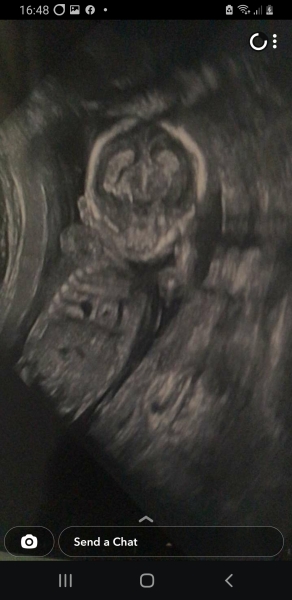

Cystic space on baby heart

Hi mums, I went for a gender scan privately yesterday and unfortunately instead of finding out gender we were told baby has a cystic space on heart. We have been referred to foetal medicine unit and have a scan Thursday. I'm 17 weeks. Has anybody ever experienced this? My downs and Edwards tests came back 1 in 100,000, but the sonographers seemed to be really concerned and kept saying "im so sorry" but wouldn't give us any more information. Now I'm left thinking my baby is ill or is not going to make it. I can't find nothing online about heart cysts only stomach or brain. On my notes it says cystic space adjacent to the heart. Has anyone experienced this and what was the outcome please? I'm so worried and so upset.